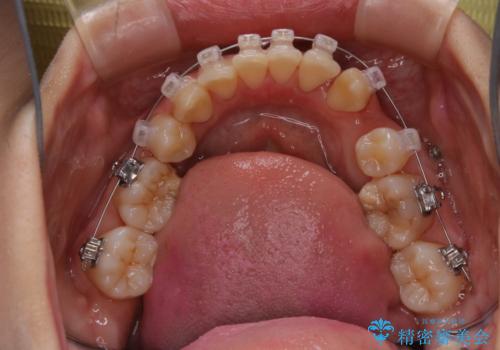

- ワイヤー矯正中に、口臭や汚れが気になり綺麗にクリーニングしたいとのことでした。染め出しをしての歯磨き指導とPMTC60分コースを行いました。

ワイヤー矯正中はブラッシングが難しくなるため、磨き残しが多くなることがあります。

ご自身でのブラッシングケアでは、歯周ポケットの中に歯ブラシの毛先が届くのはわずか2ミリ程です。軽度の歯周炎の場合でも歯周ポケットは3ミリほどあります。歯茎の中に長く汚れが溜まると、歯石や細菌などがつき、口臭の原因にもなります。

適切な道具を使って、適切なブラッシング方法を習得することで、磨き残しを減らすことができます。

また、矯正で歯の移動があると今までなかったところに隙間が出てきたり、ガタつきが解消されてきたりすることで、お口の中の環境が変わります。

矯正治療中も清潔な口腔内を保つことは、とても大切です。そのため、定期的に専門的な機械・材料を使用したProfessinnalcleaning(pmtc)を行うことがおススメです。